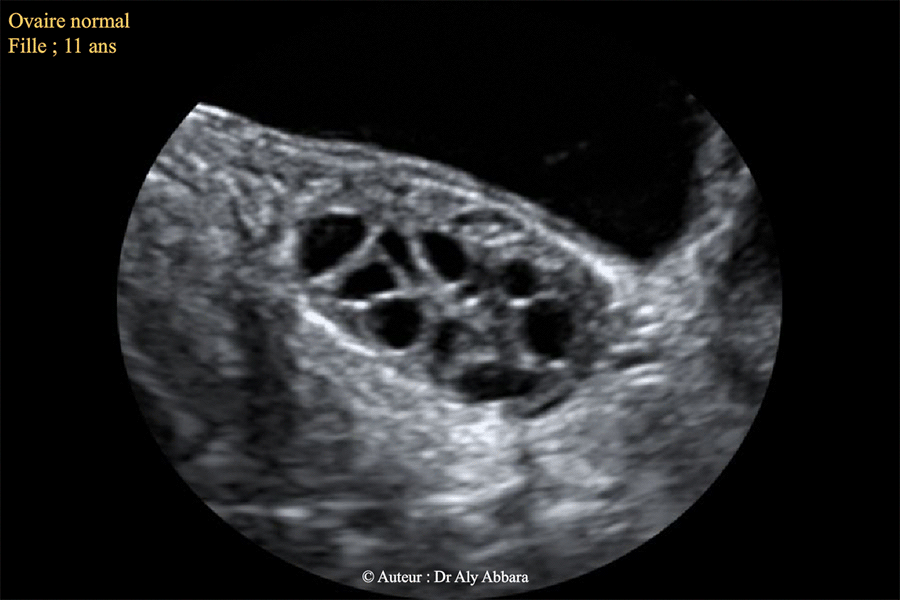

L'aspect échographique d'un ovaire normal chez une fille de 11 ans

Images échographiques d'un ovaire (gauche) normal chez une fille de 11 ans (non encore réglée - pas de ménarche).

Il s'agit d'un ovaire mesurant 35 x 22 x 20 mm de diamètre, soit 8 cm3 de volume, contenant au sein de son stroma de très nombreux follicules antraux (de 2 à 5 mm de diamètre).

A signaler que cette image a été obtenue dans un contexte de torsion nécrosante des annexes utérines controlatérales (droites)